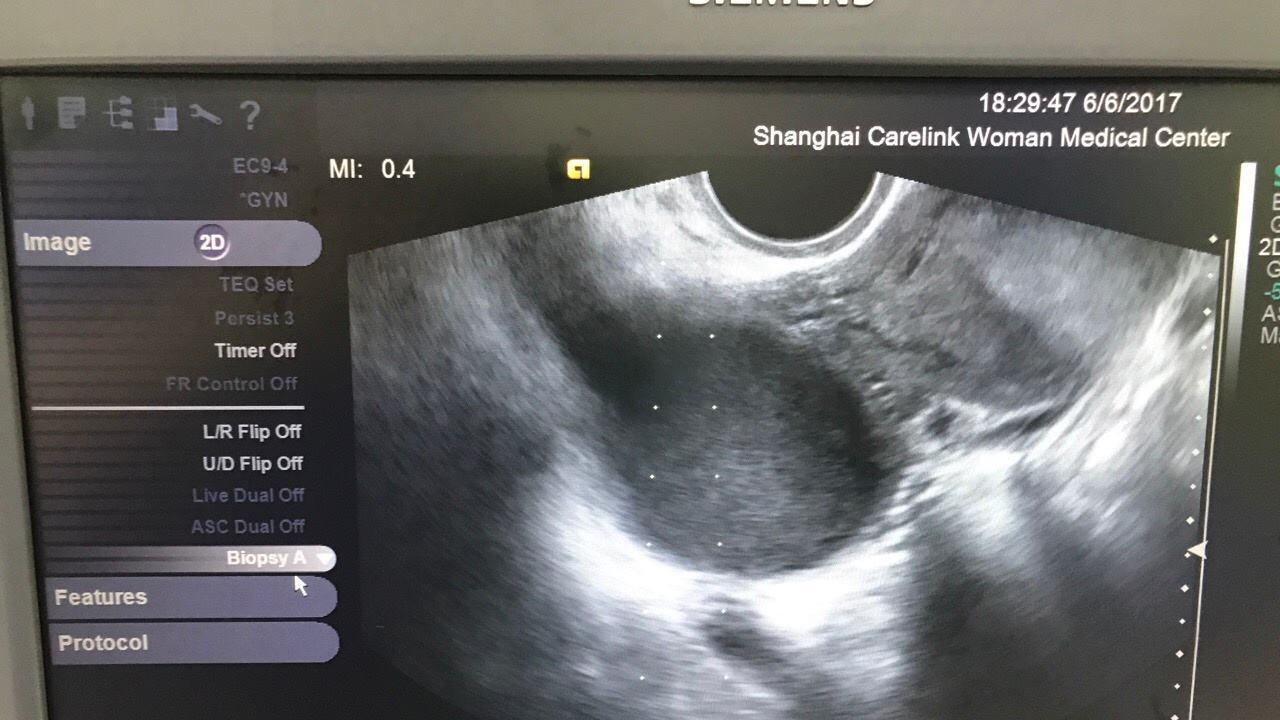

一般的脱垂,都是轻度子宫脱垂,确诊需要使用阴道镜检查,一般如果发现宫颈位于坐骨棘下方、和处女膜距离小于4cm则为子宫脱垂现象。